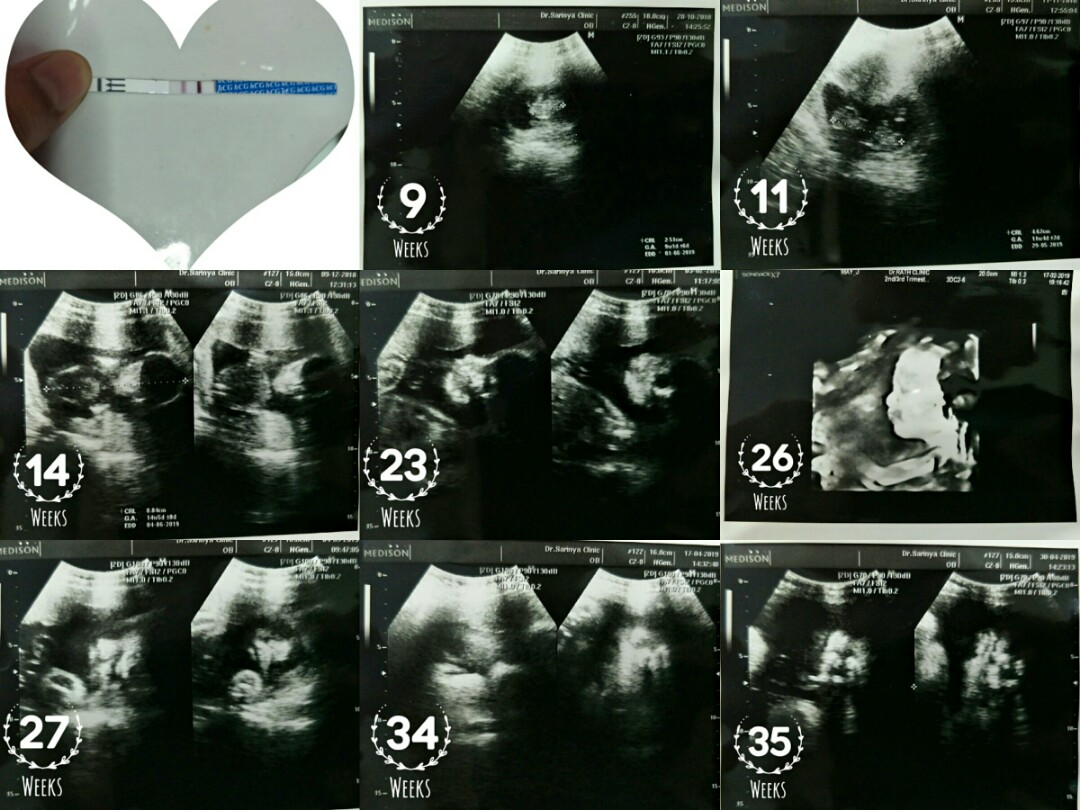

1เดือน